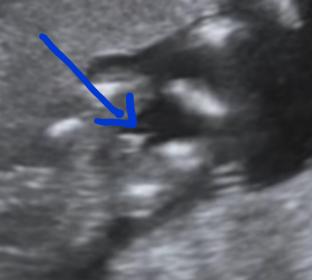

A friend of another group helped me with my video screening two new images confirming boy. What do you think my friends? 100% boy?

The other pick

This does look boyish, but your video is difficult, as I've seen some labia where I was sure it was a boy, but it was a girl. But I think 80% boy for you.

New image from my friend Attachment 32100